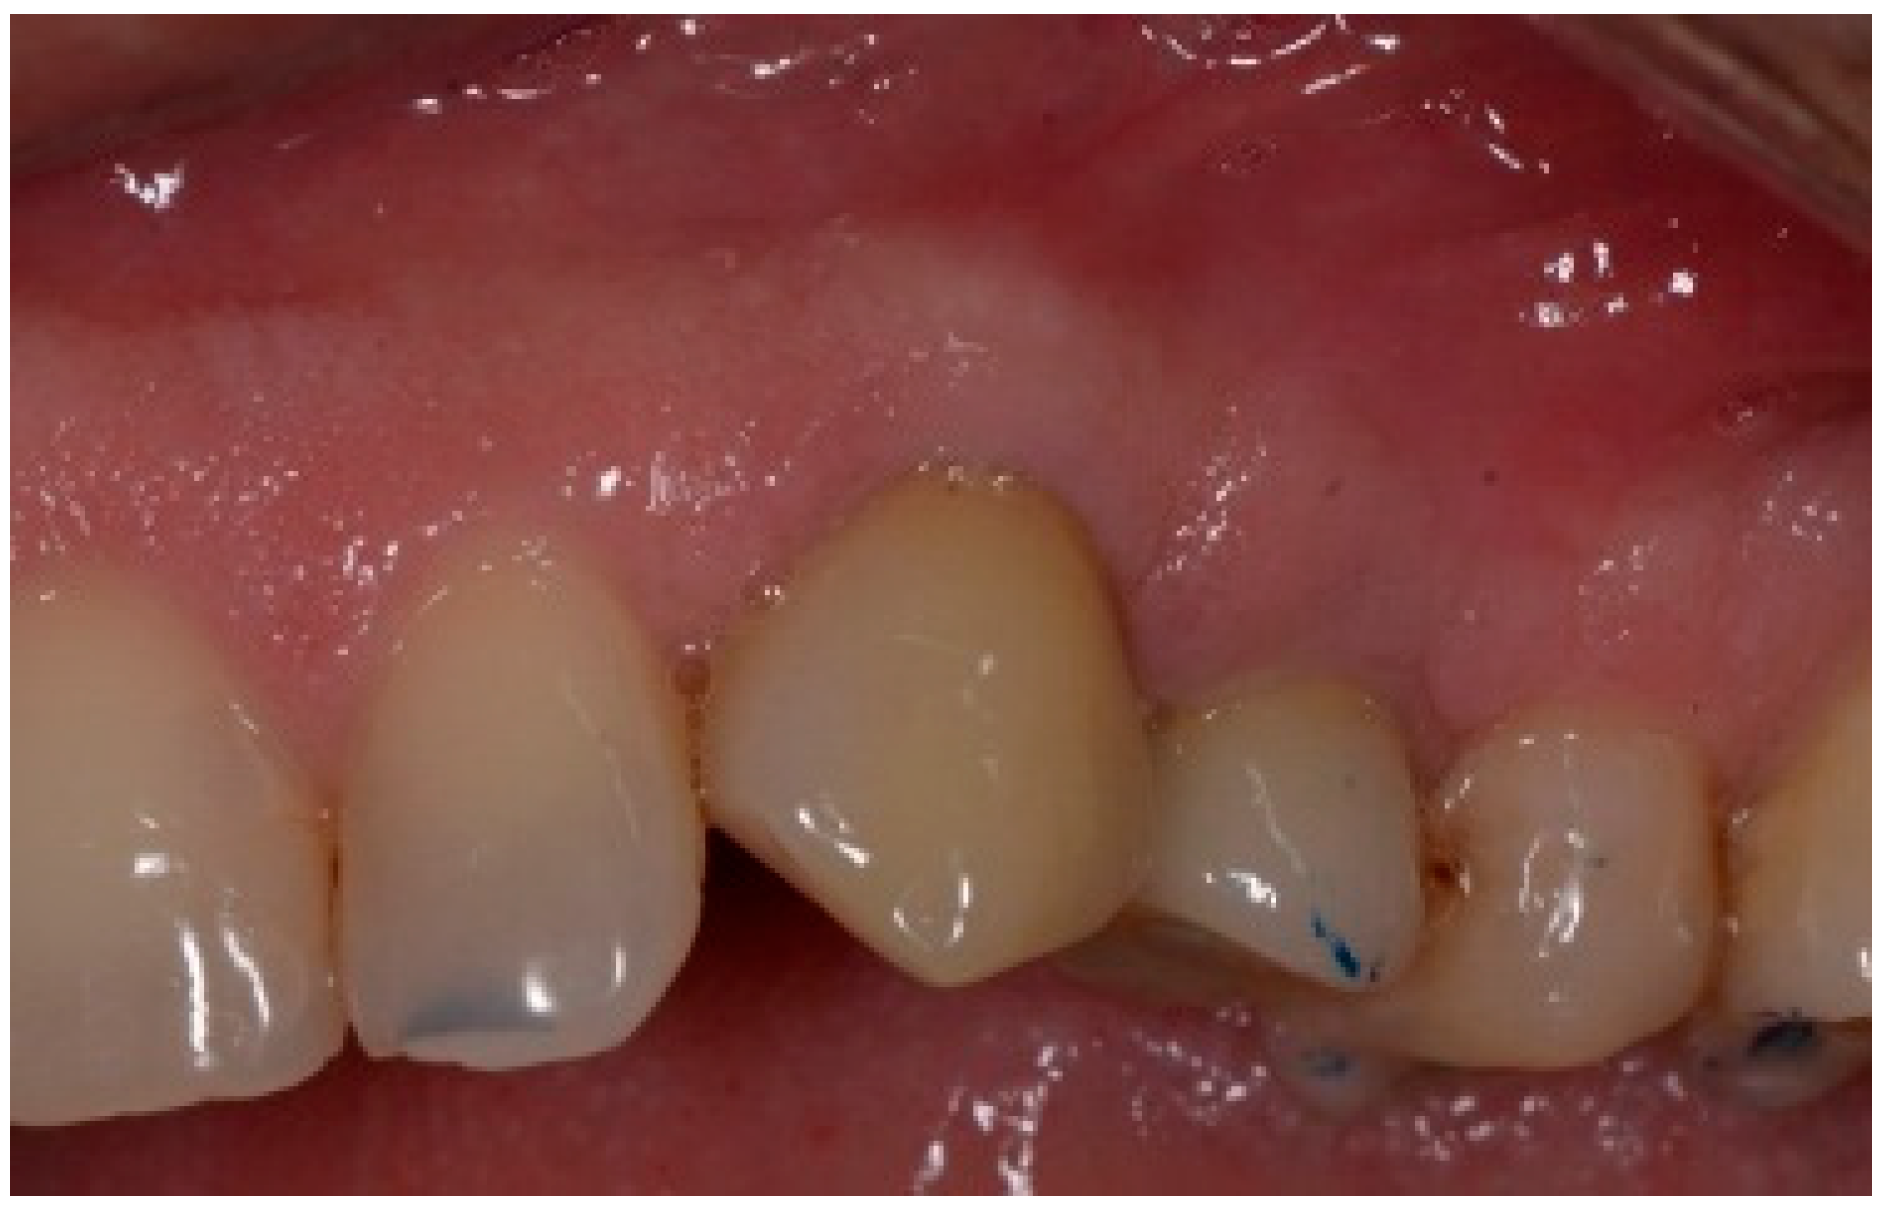

A 50-year-old female in good health and a non-smoker presented to our clinic with a failing maxillary left central incisor (Figure 13). The treatment plan consisted of the extraction of the existing tooth and replacing it with an implant. The preoperative surgical protocol described in patient 1 was followed. An L-shaped aesthetic flap design was used, revealing a buccal wall defect (Figure 14). The implant was placed with a screw-retained chair-side temporary crown (Figure 15), followed by the placement of bone graft material over the boney defect (Figure 16). A double-layer collagen membrane was placed and the flap closed. After six months, the final ceramic crown was inserted (Figure 17).

Figure 13.

Clinical view of extraction site (note tissue above tooth #9).

Figure 14.

Clinical view of extraction site implant.